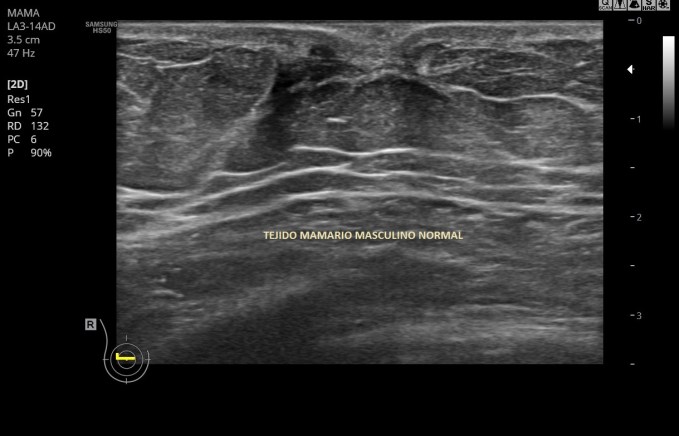

La semiología de un tumor paratiroideo habitual o Adenoma Paratiroideo hemos dicho que puede ser inéspecífica, pero podemos destacar que suelen ser ovalados, en ocasiones psudotriangular, afilado o bilobulado, son hipoecocoicos y homogéneos y un porcentaje reducido, pueden tener degeneración quística, su vascularización está aumentada.

La ecografía muestra un tiroides multinodular, porque tiene otros tipos de imágenes nodulares al margen de la lesión estudiada. Adyacente al LTD y en contacto con la carótida común se observa una lesión nodular, sólida, no es anecoica ni tiene este componente, por tanto se considera sólida, hipoecogénica, que mide 10 x 9 mm y que por su localización y morfología es compatible con un adenoma de paratiroides inferior derecha, anatómicamente suelen ser 4, dos por lóbulo, una en polo superior y otra en el inferior…Hasta el próximo Post.